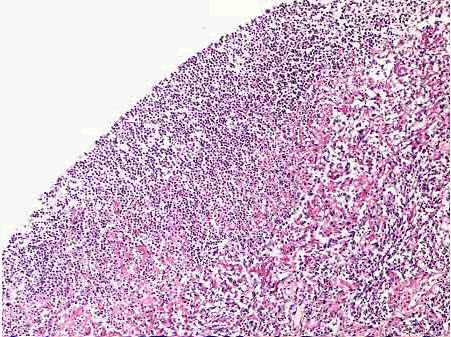

201、单项选择题

死者,女性,68岁,长期胸闷不适,进行性加剧至心衰而亡。

死后心脏的大体观如图所示,病理诊断应为()“

A.化脓性心包炎

B.纤维素性心包炎

C.心肌炎

D.心肌梗死

E.以上均不是